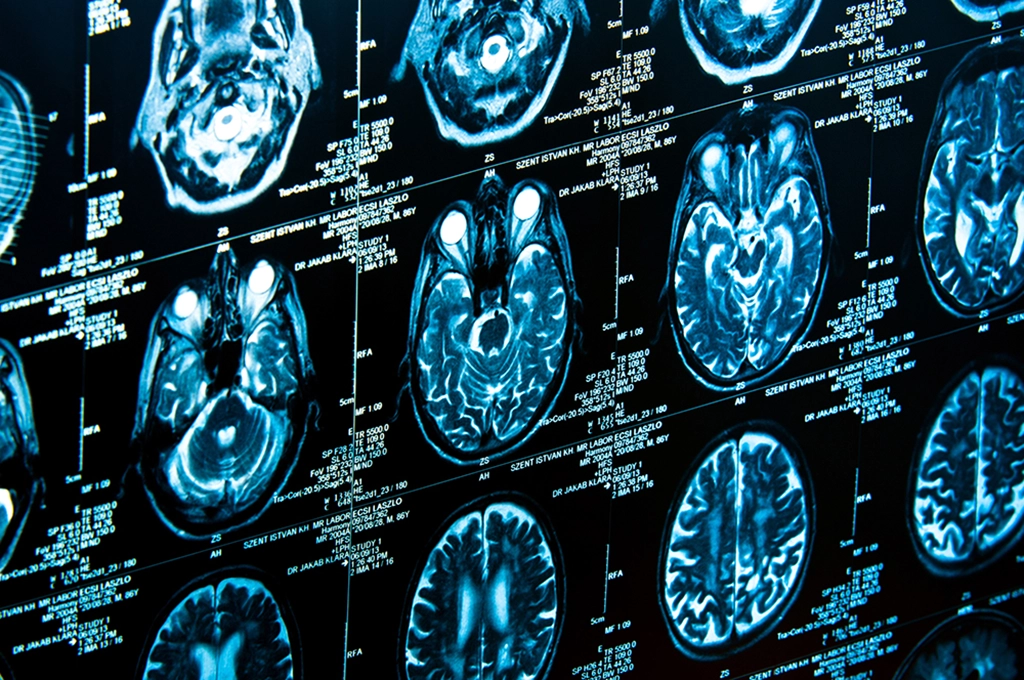

wallpaperaccess.comWhat A CT Scan Shows Of The Head & Brain

wallpaperaccess.comWhat A CT Scan Shows Of The Head & Brain